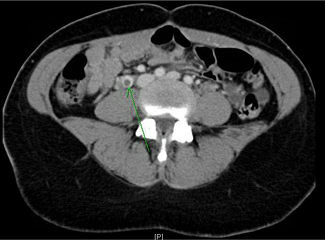

CT scans of the abdomen and pelvis (Figures 1-3) revealed bilateral ovarian vein thrombosis, worse on the right side than the left. A heparin infusion was immediately started to prevent a pulmonary embolism and therapy with broad-spectrum antibiotics (gentamicin and clindamycin) was also initiated.

Figure 1